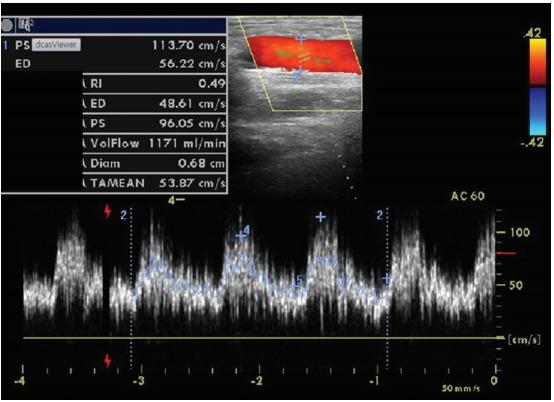

Logistic regression analysis showed that brachial artery flow volume (FV) < 612.9 mL/min or brachial artery resistance index (RI) > 0.63 was independently associated with the need for PTA. This monitoring strategy showed an a reduction in thromboses (0.02 ± 0.11 events/arteriovenous fistula [AVF]-year vs. 0.07 ± 0.23 events/AVF-year, p = 0.046), reduction in central venous catheter placement (0.01 ± 0.05 events/AVF-year vs. 0.06 ± 0.22 events/AVF-year, p = 0.010), reduction in access loss (0.02 ± 0.13 events/AVF-year vs. 0.19 ± 0.34 events/AVF-year, p = 0.015), and increase in access selective repair (0.49 ± 0.66 events/AVF-year vs. 0.21 ± 0.69 events/AVF-year, p = 0.003), compared to historic control.

There was significant stenosis if brachial artery FV was < 612.9 mL/min or RI was > 0.63 for PE abnormality. These parameters should be used as markers for assessing PTA risk in hemodialysis patients. Addition of USG to determine the need of angiography after detection of PE abnormality leads to decreases in access thrombosis, catheter placement, and access loss despite increasing access intervention rates compared to clinical monitoring.

逻辑回归分析显示,肱动脉流量(FV)<612.9mL/min 或肱动脉阻力指数(RI)>0.63 与 PTA 需求独立相关。该监测策略显示血栓形成减少(0.02±0.11 事件/动静脉瘘[AVF]-年 vs. 0.07±0.23 事件/AVF-年,p=0.046)、中央静脉导管放置减少(0.01±0.05 事件/AVF-年 vs. 0.06±0.22 事件/AVF-年,p=0.010)、血管通路丧失减少(0.02±0.13 事件/AVF-年 vs. 0.19±0.34 事件/AVF-年,p=0.015)和血管通路选择性修复增加(0.49±0.66 事件/AVF-年 vs. 0.21±0.69 事件/AVF-年,p=0.003),与历史对照相比。

PE 异常时,如果肱动脉 FV<612.9mL/min 或 RI>0.63,则存在显著狭窄。这些参数可作为评估血液透析患者 PTA 风险的标志物。与临床监测相比,在检测到 PE 异常后,通过 USG 确定是否需要血管造影可以减少血管通路血栓形成、导管放置和血管通路丧失,尽管血管通路干预率增加。